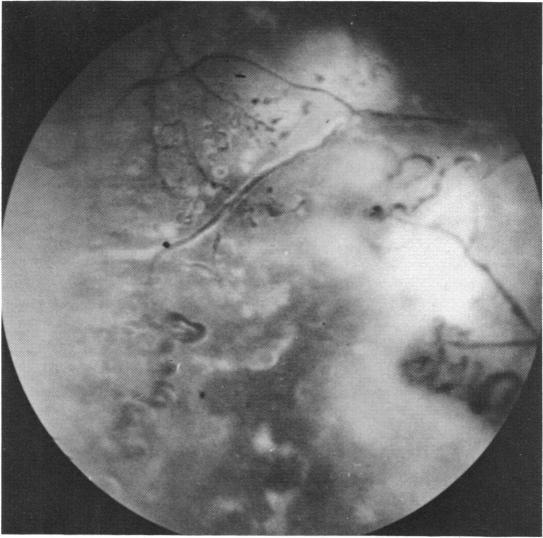

Coats' disease and congenital vascular retinopathy.

Trans Am Ophthalmol Soc. 1976;74:365-424.